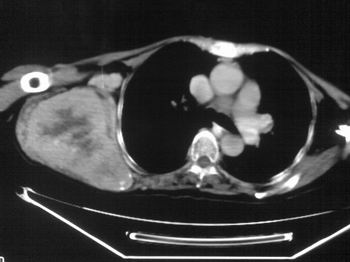

以下是引用zhangxu5888在2007-9-11 16:25:00的发言:[br]有侧肩胛骨溶骨性破坏且见软组织成分,增强软组织强化明显,中央见低密度坏死区!根据病史10年,考虑良性肿瘤恶性变!性质待定!

以下是引用老爱克斯新网客在2007-9-11 18:22:00的发言:[br]应该是良性肿瘤恶变,但因晚期破坏严重不能见到原来肿瘤征象无法判断,